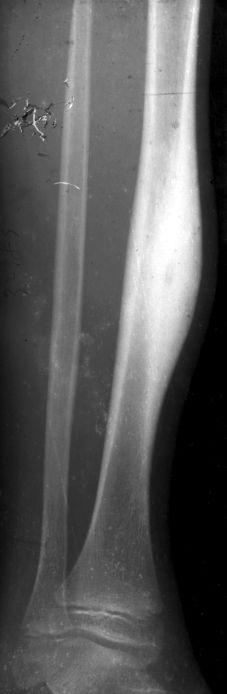

在上 1/3 折,由于儒腰肌、臀中肌、臀小肌和外旋肌的牵拉,使近折端向前、外及外旋方向移位;远折端则由于内收肌的牵拉而向内、后方向移位;由于股四头、阔筋膜张肌及内收 的共同 用而向近端移位。

中 1/3 骨折后,由于内收肌群的牵拉,使骨折向外成角

下 1/3 骨折后,远折端由于排肠肌的牵拉以及肢体的重力作用而向后方移位,又由于股前、外、内 牵拉的合 ,使近折端向前移位,断端重叠,形成短缩畸形

非手术治疗 3岁以下儿 采用垂直悬吊皮肤牵引在牵引过程中,要定时测量肢体长度和进行床旁X线检查,了解牵 力是否足够。若牵引力过大,导致过度牵引,骨折端出现裂隙,将会发生骨折延迟愈合或不愈合。;成人和3岁以上 的股骨干骨折近年来多采用手术内固定治疗 对于存在于术 忌证的,可行持续 10 卧床期间,需肌肉收缩训练,预防肉萎缩、关节粘连和深静脉血栓形成。床旁X线平片证实骨折愈合后,下地活动

手术治疗 成人股骨干骨折于术多采用钢板、带锁髓内钉固定。儿童股骨干骨折多采用弹性钉内固定;严重的开放性骨折可用外固定架治疗